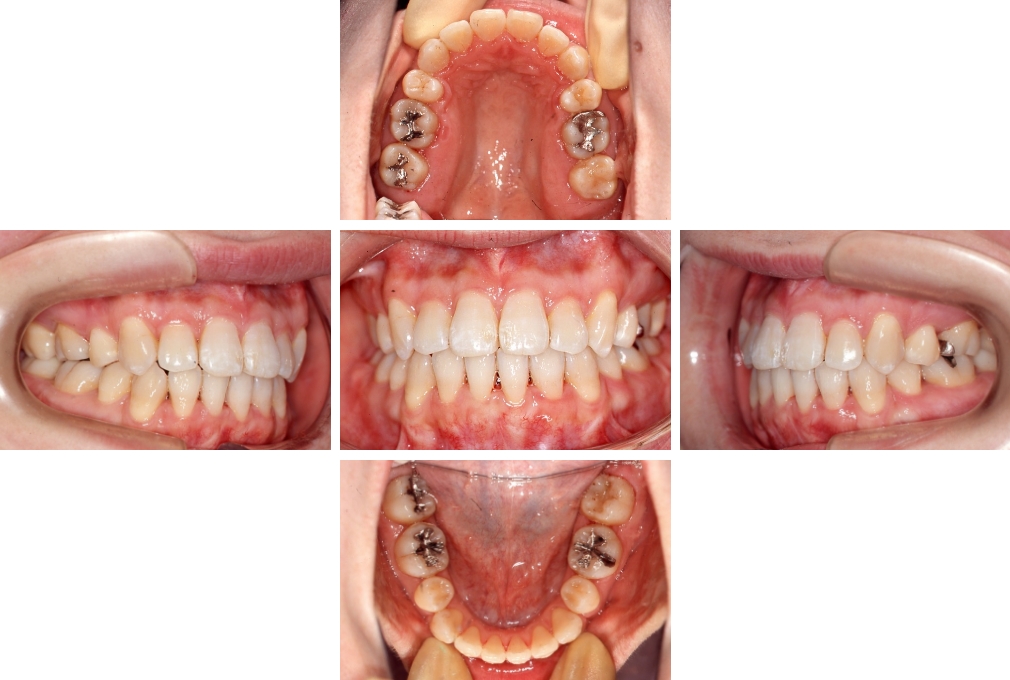

CASE:03

上下顎前突

初診時年齢 18歳4か月

性別 男性

治療費の目安 105万円程度(治療開始時)

歯列の乱れは著しくなく上顎右側側切歯が捻転し口蓋側へ転位していた。また、問診の中で患者さんから最も重視する治療結果として口元の突出の改善の申出があった。下顎が後退した上顎前突傾向ではあったが著しいものではなかった。上下顎前突と診断し上下顎小臼歯抜歯を行っていただき、上下顎舌側マルチブラケット装置を使用して、矯正用アンカースクリューを併用して動的治療を行った。上下顎前歯の後退を十分行い口元の突出感も改善した。治療後10年1か月の来院時には口元の突出感が再発することもなく、下顎前歯の少しの唇舌的なずれはあったが歯列は安定していた。動的治療期間2年2ヵ月間。

治療前

18歳4ヵ月

治療後

動的治療期間2年2カ月間

20歳10か月

10年経過

動的治療終了後10年1カ月

30歳11か月